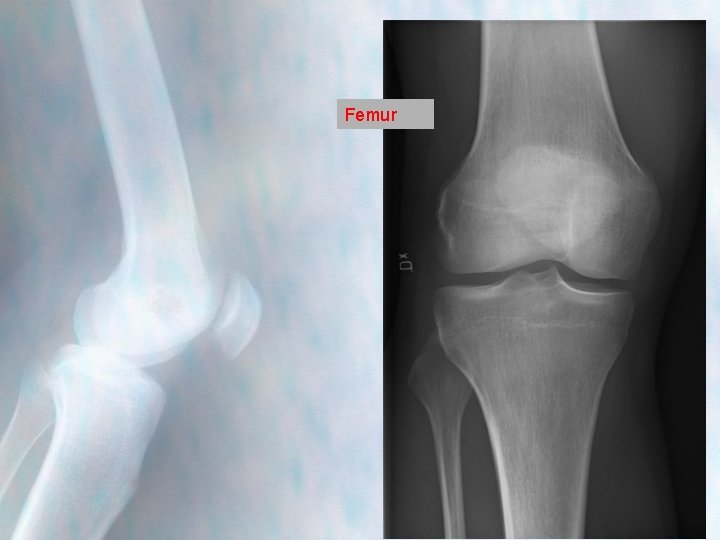

Femur

AP Should always be in weight bearing, and both knees Alignment – Lateral tibial line (lateral edge of tibia and lateral edge of the femoral condyle should be aligned) – The tibial plateau is not flat but slopes at about 15° downwards from anterior to posterior.

AP good position -Knee in full extn -Leg in neutral rotation